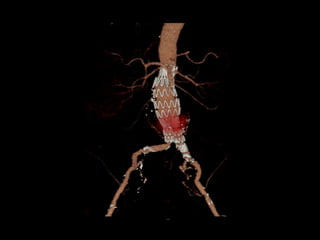

OptionsOptions

??

http://www.perfuse.netVascular surgery @ Tallaght